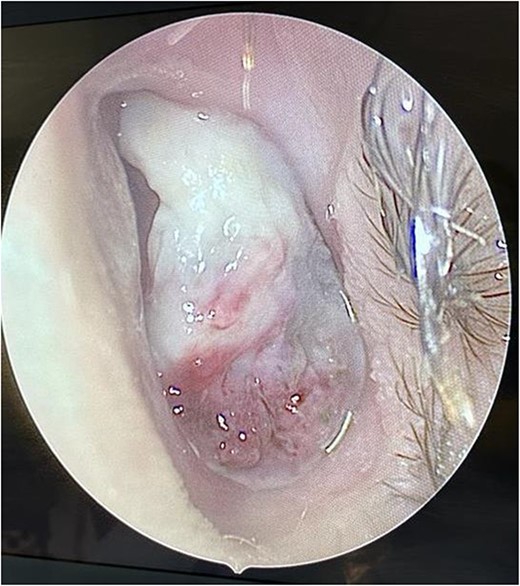

We present a case of a medically free 13-year-old male, who presented to the emergency department with a left-sided epistaxis for 2 days. Notably, the episodes of epistaxis resolve spontaneously after 5 to 10 min, without applying pressure. Also, the patient complained of on and off left-sided nasal obstruction, and denied history of dizziness, loss of consciousness, and choking. Upon physical examination, the patient was vitally stable, looking well, not cyanosed, nor having cervical lymph node enlargement. Nasal speculum examination showed left intra-nasal mass obstructing the cavity. Routine laboratory investigations yielded a hemoglobin (Hgb) level 0f 141g/L, white blood cell count of 7.30 K/μl, INR of 1.02, prothrombin time (PT) of 11.40 s, and partial thrombin time (PTT) of 28.30 s. Initially, the patient was radiologically investigated by paranasal sinuses (PNS) computed tomography (CT) which demonstrated an enhancing lesion involving the left nasal cavity. An MRI was performed demonstrating an oval-shaped mass filling the anterior nasal cavity, the lesion was measuring ~3 × 1.1 × 2.5 cm in anteroposterior, transverse, and craniocaudal dimension, respectively (Fig. 1). Intra-operative nasal cavity along with postnasal space examination was decided to be performed along with left nasal mass excisional biopsy under general anesthesia. Intraoperative examination of the nasal cavity using a zero-degree rigid endoscope showed a fragile left nasal mass (Fig. 2). The lesion was bleeding heavily; thus, cauterization was performed to control bleeding before taking the biopsy. The patient had an uneventful postoperative course. Histopathological evaluation showed the characteristic polypoidal lesion composing of capillary proliferation in a background of fibromyxoid stroma and granulation tissue, arranged in a lobular pattern.

Intra-operative endoscopic findings of the left nasal cavity, showing a vascularized mass occupying the left nasal cavity.